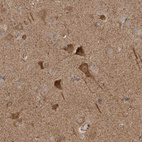

Immunohistochemical staining of human cerebral cortex shows moderate to strong cytoplasmic positivity in neurons.